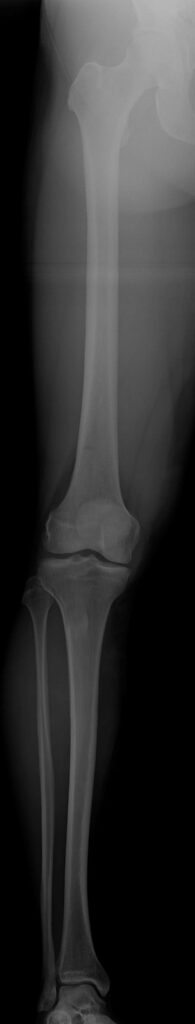

Varus-Fehlstellung (O-Bein)

Fehlstellungen der Gelenkachse können sowohl angeboren sein, als auch durch Verletzungen oder Krankheiten entstehen. Zu den Ursachen von Achsenfehlstellungen zählen beispielsweise schlecht verheilte Knochenbrüche, Gelenksentzündungen und Rachitis. Sowohl X-Bein- als auch O-Bein-Fehlstellungen führen in weitere Folge zu sekundär degenerativen Schäden, wie Meniskusschäden oder einseitige Knorpelschäden, welche von Knieschmerzen begleitet werden. Achsenfehlstellungen, wie O-Bein- und X-Bein-Fehlstellungen, gelten erwiesenermaßen als „präarthrotische Deformität“, das heißt, dass diese in weiterer Folge zu Abnutzungserscheinungen, wie Arthrose führen und deshalb dringend korrigiert werden sollten.

Um Achsenfehlstellungen, wie O-Bein- und X-Bein-Fehlstellungen, welche zu einer Fehlstellung des Knies führen, zu diagnostizieren, müssen primär klinische Untersuchungen erfolgen: die Untersuchung des Gangbildes, des Bewegungsumfangs und der Beinachse sowie Tests rund um den Meniskus. Nach der klinischen Untersuchung können technische Untersuchungen erfolgen: Achsenfehlstellungen der Beine werden mithilfe eines MRT diagnostiziert. Des Weiteren können Ganzbeinaufnahmen im Stehen und Röntgen des Kniegelenks in zwei Ebenen Aufschluss über das Ausmaß der Fehlstellung liefern. Ergänzend wird in manchen Fällen eine präoperative Arthroskopie durchgeführt.